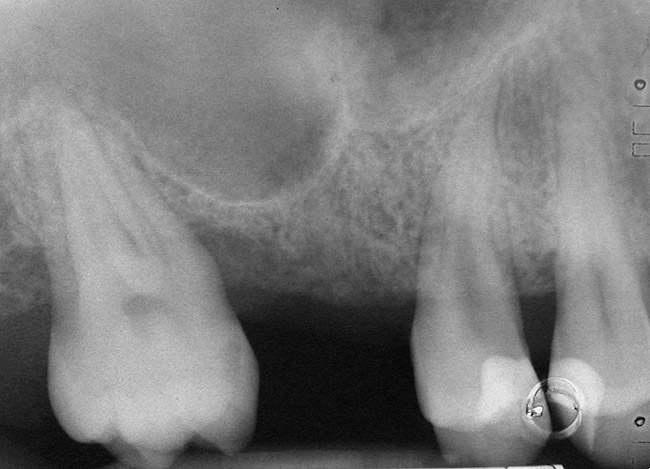

A 45-year-old female was referred for implant placement and prosthetic treatment in the area of tooth No. 24. The tooth had been extracted 4 years prior; the patient did not wear any denture thereafter. The radiograph revealed adequate bone height and a 5-mm to 6-mm ridge at the crest (Figure 2). It was decided to place a 11.5 mm in length, 3.75 mm in diameter Tapered Screw-Vent® implant (Zimmer Dental, www.zimmerdental.com) using the alveolar remodeling technique in the area of tooth No. 24.

Figure 2  Preoperative view of the area around tooth No. 24. On the left, a previously placed implant abutment is visible.

Figure 2